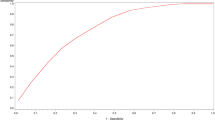

According to the inclusion criteria, 201 cancer patients with COVID-19, including 36 variables indices, were included in the analysis. The top eight indices (albumin, lactate dehydrogenase, cystatin C, neutrophil count, creatine kinase isoenzyme, red blood cell distribution width, D-dimer and chest computed tomography) for predicting the occurrence of ACI in cancer patients with COVID-19 infection were included in the RF model. The model achieved an area under curve (AUC) of 0.940, an accuracy of 0.866, a sensitivity of 0.750 and a specificity of 0.900. The calibration curve and decision curve analysis showed good calibration and clinical practicability. SHAP results demonstrated that albumin was the most important index for predicting the occurrence of ACI. LIME results showed that the model could predict the probability of ACI in each cancer patient infected with COVID-19 individually.